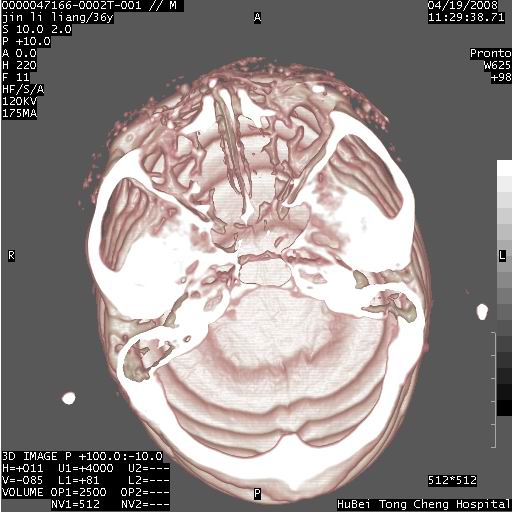

患者 男,36岁。头面部“土炮”炸伤。pe:面目全非,伤口流血不止。

临床诊断:头面部外伤。

颅脑ct轴位平扫(层厚、层距均为10mm),图像如下:

左眼球破裂并异物,眶周、额顶部头皮及软组织挫伤并异物

迎面一炮,满脸开曝。额顶部头皮及软组织挫伤并异物,左眼球破裂积气并异物,典型的面目全非,惨不忍睹。

1左侧眼球破裂并积气,球内、框内异物。

2额部顶部软组织伤。